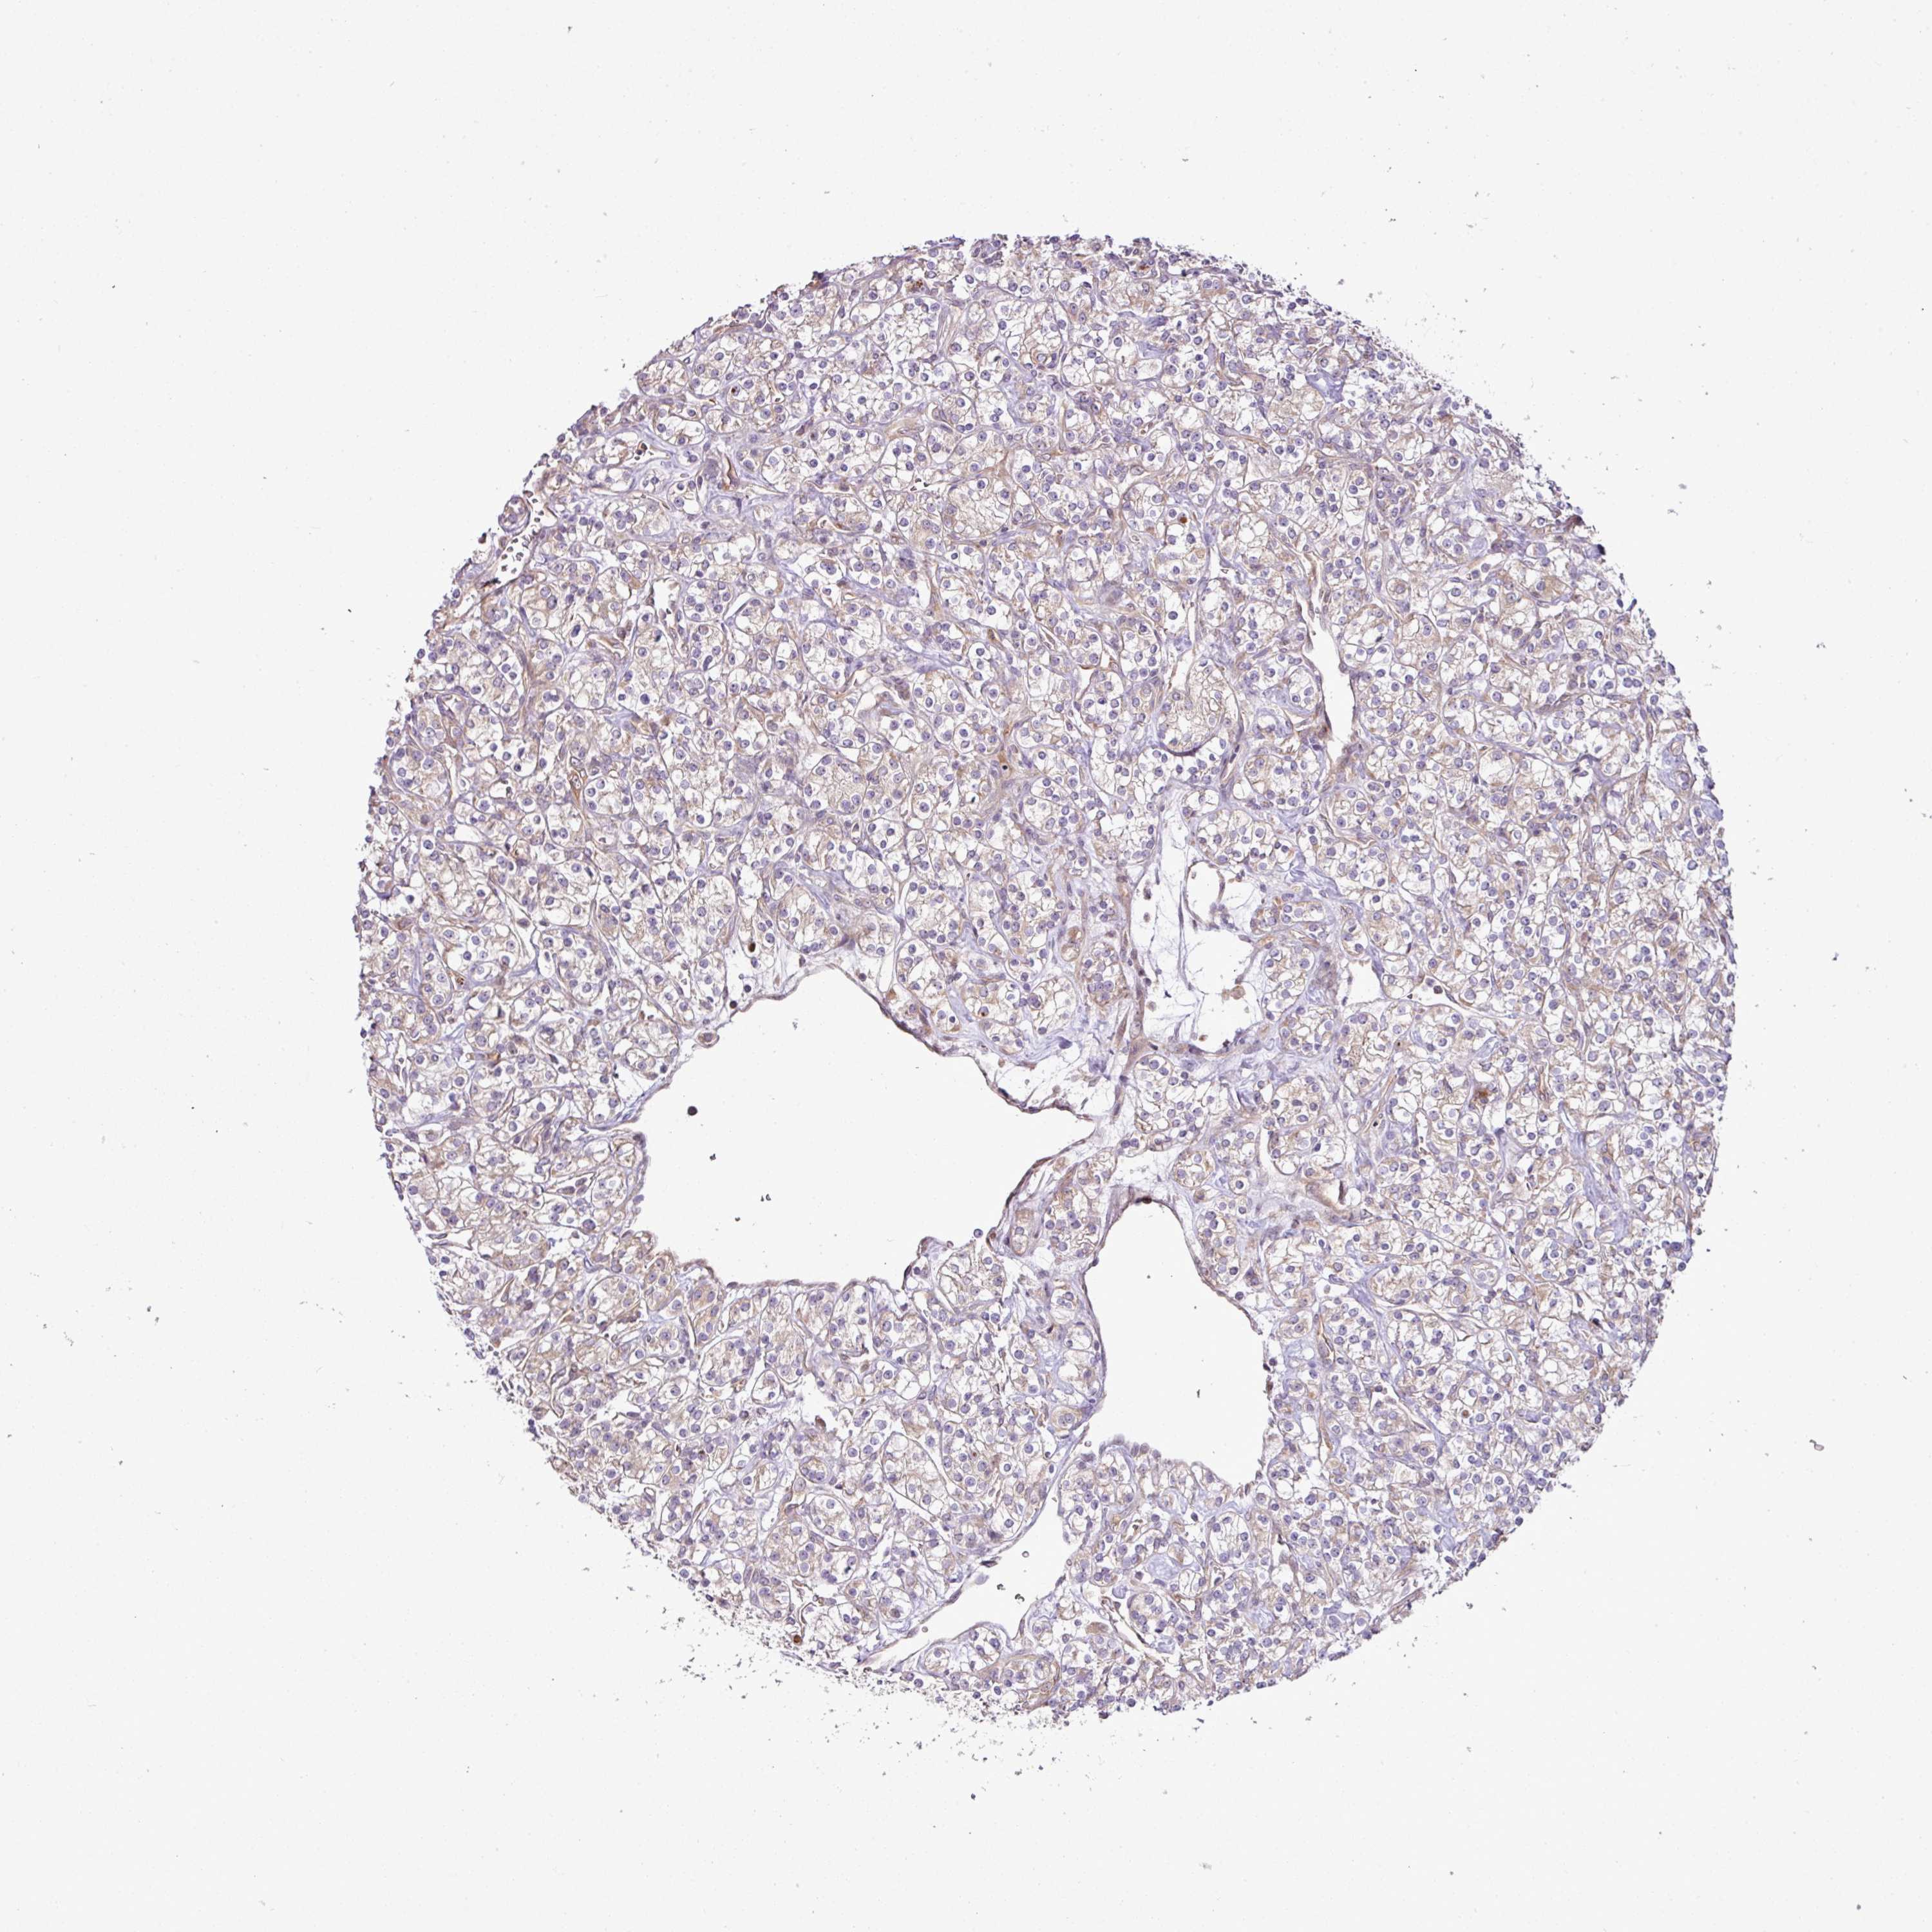

KIDNEY RENAL CLEAR CELL CARCINOMA (VALIDATION) - Interactive survival scatter ploti

The Survival Scatter plot shows the clinical status (i.e. dead or alive) for all individuals in the patient cohort, based on the same data that underlies the corresponding Kaplan-Meier plots. Patients that are alive at last time for follow-up are shown in blue and patients who have died during the study are shown in red.

The x-axis shows the expression levels (FPKM) of the investigated gene in the tumor tissue at the time of diagnosis. The y-axis shows the follow-up time after diagnosis (years). Both axes are complimented with kernel density curves demonstrating the data density over the axes. The top density plot shows the expression levels (FPKM) distribution among dead (red) and alive patients (blue). The right density plot shows the data density of the survived years of dead patients with high and low expression levels respectively, stratified using the cutoff indicated by the vertical dashed line through the Survival Scatter plot. This cutoff is automatically defined based on the FPKM cutoff that minimizes the p-score. The cutoff can be changed by dragging the vertical line or by entering a cutoff value in the square labeled "Current cut-off".

Under the Survival Scatter plot the p-score landscape (black curve; left axis) is shown together with dead median separation (red curve; right axis). Dead median separation is the difference in median mRNA expression between patients who have died with high and low expression, respectively. It is calculated as follows: median FPKM expression of dead patients with high expression - median FPKM expression of dead patients with low expression. This is intended to aid the user in visually exploring custom cutoffs and the associated p-scores and dead median separation.

Individual patient data is displayed and can be filtered by clicking on one or more of the category buttons on the top of the page. Categories describing expression level and patient information include: high, low, alive, dead, female, male and tumor stages. The scale of the x-axis can be toggled between linear and log-scale by clicking on the "x log" button. Mouse-over function shows TCGA ID, patient information and mRNA expression (FPKM) for each patient.

& Survival analysisi

Kaplan-Meier plots summarize results from analysis of correlation between mRNA expression level and patient survival. Patients were divided based on level of expression into one of the two groups "low" (under cut off) or "high" (over cut off). X-axis shows time for survival (years) and y-axis shows the probability of survival, where 1.0 corresponds to 100 percent.

COX18 is not prognostic in Kidney Renal Clear Cell Carcinoma (validation)

TCGA RNA samplesi

RNA-seq data is reported as average FPKM (number Fragments Per Kilobase of exon per Million reads), generated by the The Cancer Genome Atlas (TCGA) .

Normal distribution across the dataset is visualized with box plots, shown as median and 25th and 75th percentiles. Points are displayed as outliers if they are above or below 1.5 times the interquartile range. FPKM values of the individual samples are presented next to the box plot.

Average pTPM 0.9

Number of samples 100